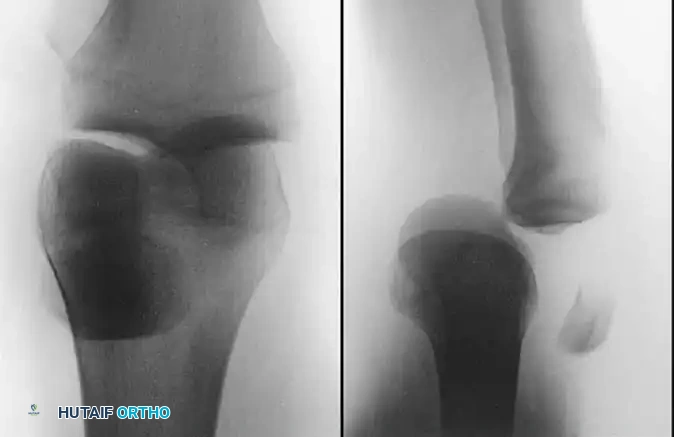

Clinical Presentation and Diagnosis

Patients with acute PTFJ dislocations usually present with localized lateral knee pain, a visible or palpable prominence in the lateral aspect of the knee, and pain exacerbated by ankle motion. Patients with chronic dislocations or subluxation complain of popping, snapping, and lateral instability, which can easily be confused with a lateral meniscus tear or snapping biceps femoris tendon. Rarely, transient or permanent peroneal nerve deficits are present due to traction on the common peroneal nerve as it wraps around the fibular neck.

KNEE Surgical Diagram

Standard anteroposterior and lateral radiographs may show subtle asymmetry or overlap of the fibular head relative to the lateral tibial condyle. However, Keogh et al. concluded after a comprehensive cadaver study that the diagnosis of suspected dislocations of the proximal tibiofibular joint is best determined with an axial CT scan, which definitively demonstrates the loss of articular congruity.